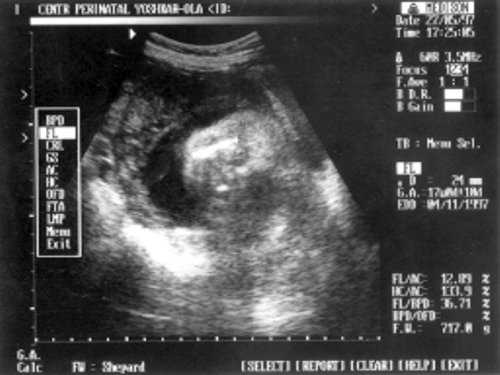

- ДБ (длина бедра) = 24 мм - 17 нед. (рис. 2)

Рис. 2. УЗИ плода - бедро.